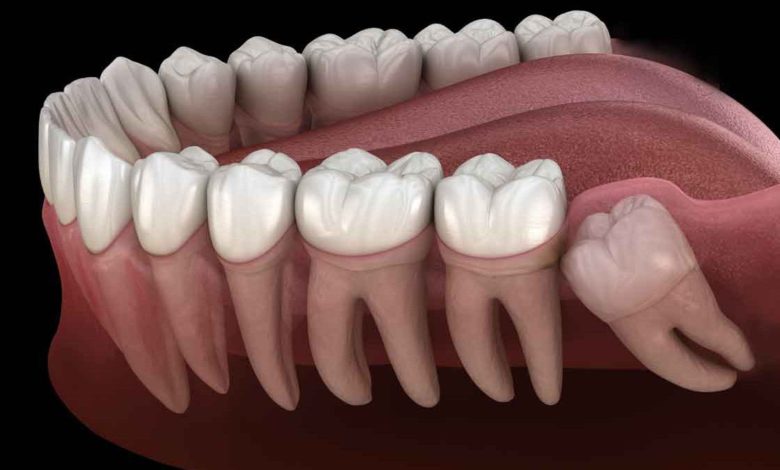

Diş Hekimi Uzunpınar, “Ortodonti, dişlerin çene ardındaki çapraşıklıklarının tedavisini içeren bilim dalı. Çapraşık dişler sadece istenmeyen estetik bir görünüme sebep olmaz; aynı zamanda ne kadar iyi bakılırsa bakılsın, ne kadar iyi fırçalanırsa fırçalansın, tam olarak temizlenmesi mümkün olamayacağı için ileride diş kayıplarına, çürüklere ve diş eti rahatsızlıklarına sebep olabilirler.

Yetersiz çiğneme fonksiyonu nedeniyle eklem ve mide rahatsızlıklarına da yol açabilirler. Bu nedenle sadece estetik kaygılar yüzünden değil, ağız hijyeninin sağlanabilmesi ve ileride yaşanabilecek rahatsızlıkların önüne geçmek için de ortodonti tedavileri gerekli. Bu nedenle çocuklar karışık dişlenme döneminden itibaren (6-7 yaş) mutlaka bir ortodontist tarafından muayene edilmeli.